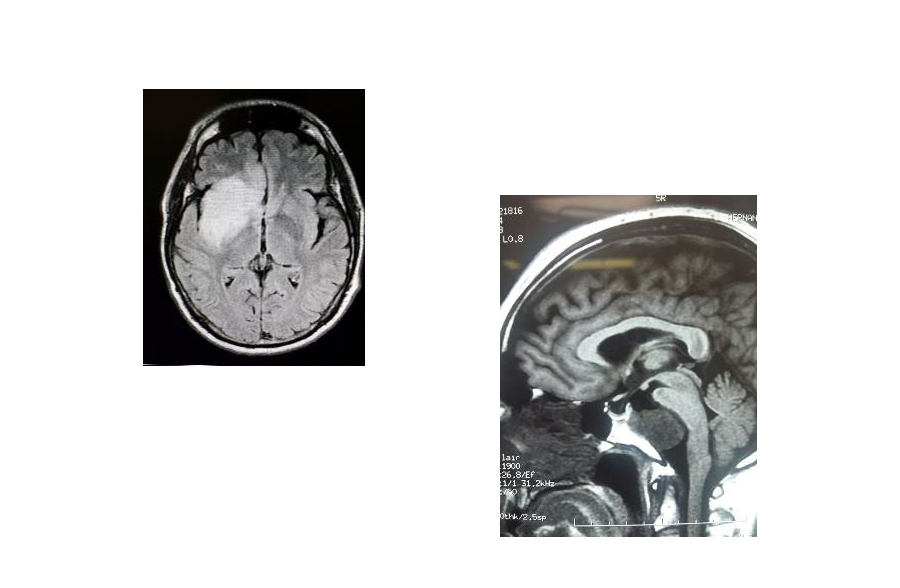

Tumores cerebrales

Los tumores se manifiestan por dolor de cabeza que no responde al manejo habitual.

También puede haber convulsiones, alteraciones de la fuerza de un lado del cuerpo o

afectación de la movilidad ocular o de la cara, vértigo, nauseas, vómitos, falta de coordinación, transtornos hormonales o visuales etc.

¡Es muy importante su detección temprana!